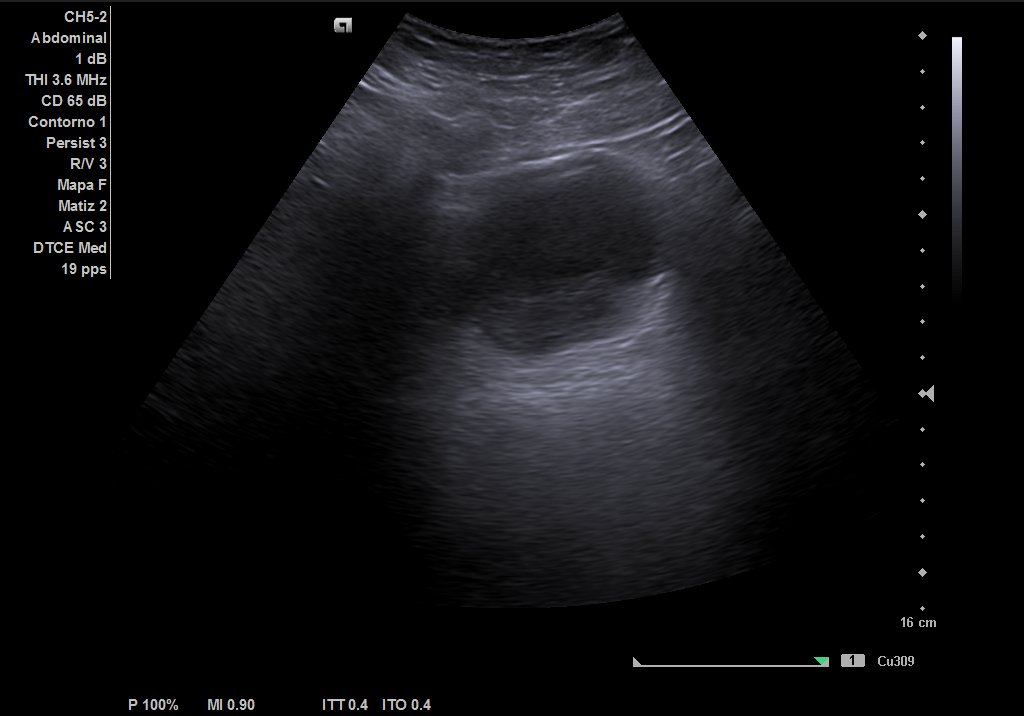

Ecografía urinaria: vejiga bien replecionada, observándose masa en trígono de 20 x 12 mm. Riñón derecho con dilatación pielocalicial moderada, sin hidronefrosis. Riñón izquierdo sin alteraciones reseñables.

Ecografía reglada: ureterohidronefrosis grado III secundaria a lesión en uréter medio-distal. Vejiga parcialmente replecionada con material ecogénico en suelo vesical con aparente doppler color e interior. Posible coágulo vs lesión subyacente.